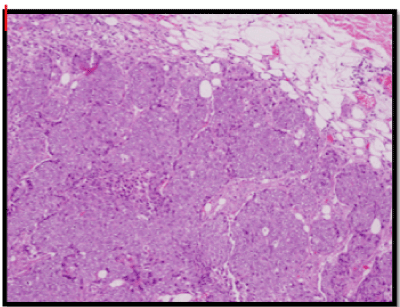

A wide local excision of the tumour was done (Figure3), which was reported as a 5x2x1.5cm irregular mass composed of cells arranged in fused glandular formation and cribriform pattern, consistent with metastatic adenocarcinoma (Slide 4). The tumour cells are positive for ER (Slide 5), PR (Slide 6), CK7, E-cadherin and mammaglobin. The immunoprofile is consistent with a metastatic breast carcinoma. The underlying skeletal muscle was uninvolved.

Slide 4. H&E Section of metastatic tumour.